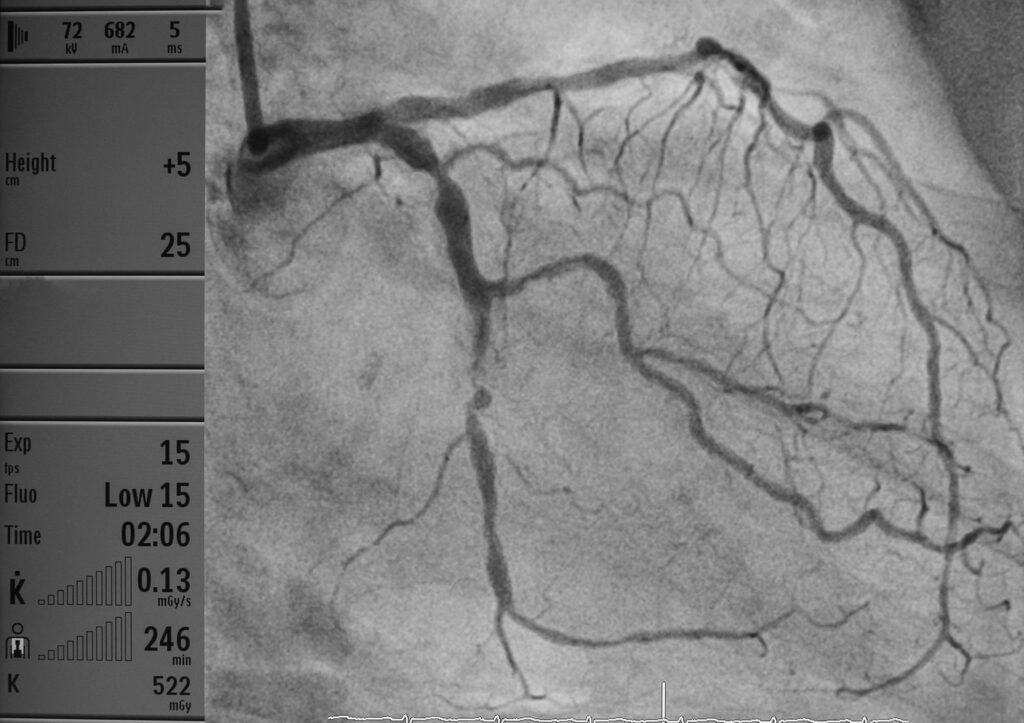

D’autres procédures courantes faisant appel à la radiologie interventionnelle sont les angiographies – une radiographie des artères et des veines pour trouver une obstruction ou un rétrécissement des vaisseaux – et les angioplasties – le placement d’un petit cathéter muni d’un ballonnet dans un vaisseau sanguin avant le gonflement du ballonnet pour ouvrir une obstruction à l’intérieur du vaisseau.

Les radiologistes d’intervention sont également responsables de la mise en place d’une endoprothèse, c’est-à-dire d’un petit tube grillagé qui aide à maintenir l’artère ouverte, réduisant ainsi les risques de rétrécissement. Le retrait de fibromes utérins fait aussi appel à la radiologie interventionnelle.